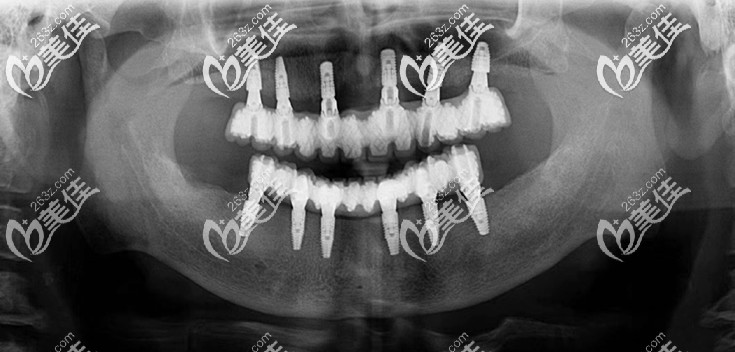

沈陽歡樂口腔全口種植牙案例效果圖:↓↓

沈陽歡樂口腔全口種植牙案例效果圖